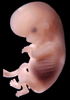

Human Embryo

Carnegie Stage 23 (56 post-ovulatory days)

Most embryos at stage 23 are approximately 56-57 postovulatory days old and measure 23-32 mm in length. Distinguishing criteria for this stage include fusion of the eyelids at the medial and lateral margins, clear distinction of the subdivisions of the upper and lower limbs, the forearms appear at or above the level of the shoulders, the superficial vascular plexus of the head is very close to the vertex, and the external genitalia are well developed but not always sufficiently to distinguish the embryo's sex.

(NOTE: These specimens are late stage 23.)